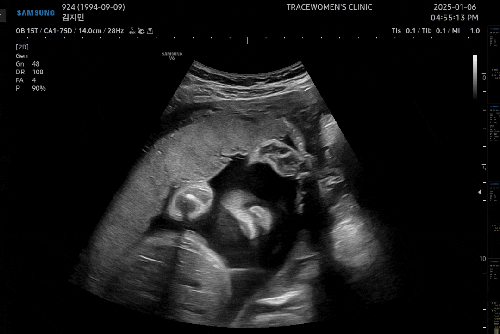

25년 1월 6일 월요일 시험관 임신 27주 2일차! * 이식일 : 24년 7월 17일 수요일 * 출산예정일 : 25년 4월 ...